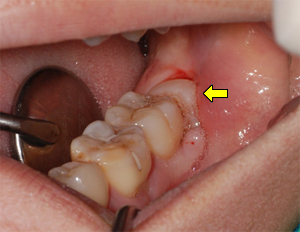

1) 우식증(충치) 여느 치아에서와 마찬가지로 불량한 위생 상태에서 발생하기 쉽다. 특히 사랑니의 경우 다른 어금니에 비해 기형인 경우가 많고 칫솔이 잘 닿지 않는 곳에 위치하기 때문에 우식증에 노출될 위험도 커진다. 초기에는 별다른 증상이 없을 수도 있지만 상아질까지 진행이 되면 냉자극에 시린 증상을 보이며, 점차 진행되어 우식의 범위가 신경조직이 있는 치수에 가까워질수록 자극에 대한 반응도 커지고 통증을 유발한다. 치수조직까지 세균이 침범하면 가만히 있어도 심한 통증이 나타난다. 2) 치관 주위염(지치 주위염) 사랑니 주위의 잇몸이나 주변 조직에 세균이 침범하여 염증을 일으킨 것으로, 맹출 중이거나 일부만 맹출 되어 잇몸조직이 치아를 부분적으로 덮고 있는 상태에서 생기기 쉽다. 주변 조직의 불편감이나 입냄새, 통증에서부터 염증으로 조직이 붉게 충혈되어 붓고 피가 나며, 농(고름)이 나오고 심할 경우 음식물을 삼키거나 입을 벌리기 곤란한 경우도 있다. 부종이 심할 경우 안면 근육 사이로 퍼져서 두개안면부 전체의 종창으로 진행하기도 한다. 3) 맹출 장애 치아가 잇몸을 뚫고 구강 내로 나오는 것을 맹출이라 하는데 사랑니의 경우 공간이 부족하여 정상적인 위치에 나오지 못하는 경우가 많다. 정상치열의 위치에서 벗어나 좌우 또는 전후로 틀어져서 비스듬히 나오거나, 일부만 나오고 일부는 잇몸 뼈에 묻히는(부분 매복) 경우도 있으며, 때로는 바로 앞 어금니(제2대구치)에 걸려서 더 이상 맹출하지 못하고 앞니 후면을 압박하는 형태로 누워 있는 수평지치 형태로 나기도 한다.

환자의 병력 청취를 통한 문진과 일상적인 방법의 구강검사를 통한 시진, 촉진 그리고 방사선 사진 촬영을 통해 대개의 진단이 가능하다. 경미한 증상은 몇 개의 치아만 볼 수 있는 치근단 사진으로 확인이 가능하나 위치 이상이나 매복, 매몰 등 전반적인 이상 유무를 확인하기 위해서는 전체 치아와 턱뼈의 상태를 한눈에 볼 수 있는 파노라마 사진 촬영이 권장된다.

제3대구치 방사선 검사